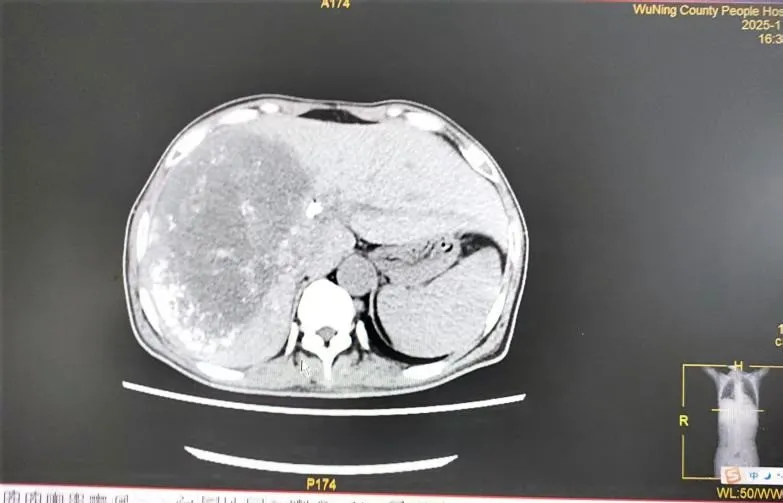

六、肿瘤科:介入综合,缓解晚期肿瘤之苦

对于已失去手术机会的晚期肝癌伴梗阻性黄疸患者,肿瘤科介入团队发挥了关键作用。一例直肠癌肝、肾上腺多发转移导致严重黄疸、肝功能受损的患者,情况危急。团队首先行“经皮胆管支架植入+引流术”,快速解除胆道梗阻,改善肝功能。待患者状况稳定后,又为其制定了序贯的“肝动脉灌注化疗联合栓塞术(HAIC+TACE)”方案。经过数次介入治疗,患者肝内转移灶明显缩小,黄疸完全消退,肿瘤标志物显著下降,生活质量得到极大改善。这凸显了我院在晚期肿瘤并发症处理及局部介入综合治疗方面的强大技术支撑。

2025年08月31日CT示:

2025年9月29日CT示:

2025年11月20日CT示: